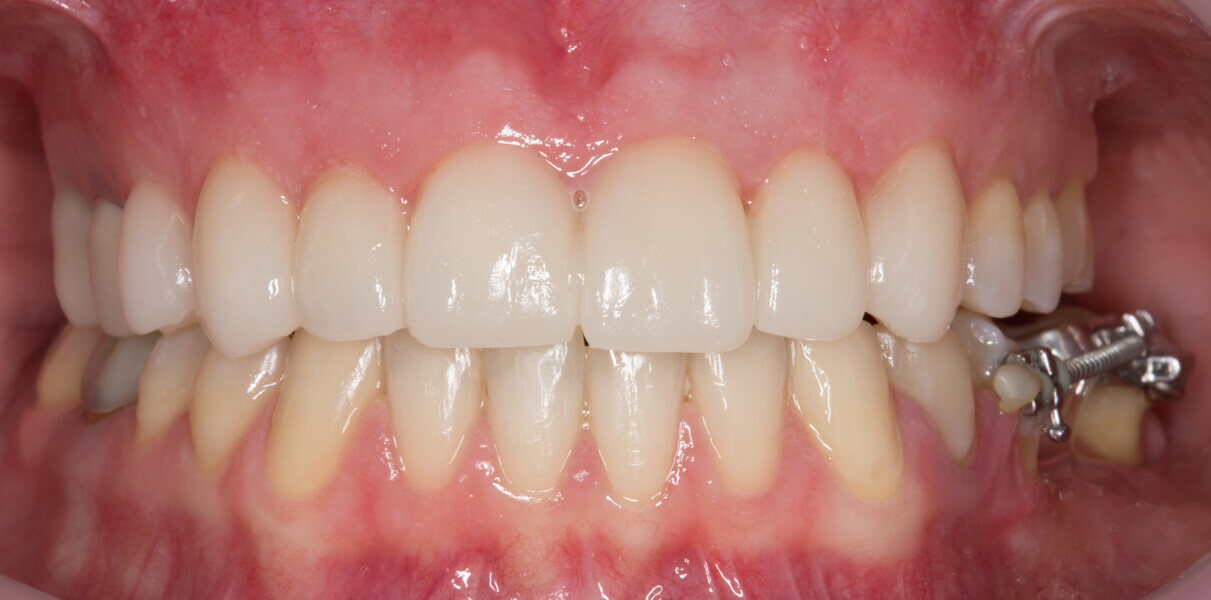

Fig. 25: Final results of the analogue and digital approach.

Fig. 26: Final results of the analogue and digital approach.

Fig. 27: Final results of the analogue and digital approach.

Fig. 28: Final results of the analogue and digital approach.

Fig. 29: Final results of the analogue and digital approach.

Fig. 30: Final results of the analogue and digital approach.

Fig. 31: Final results of the analogue and digital approach.